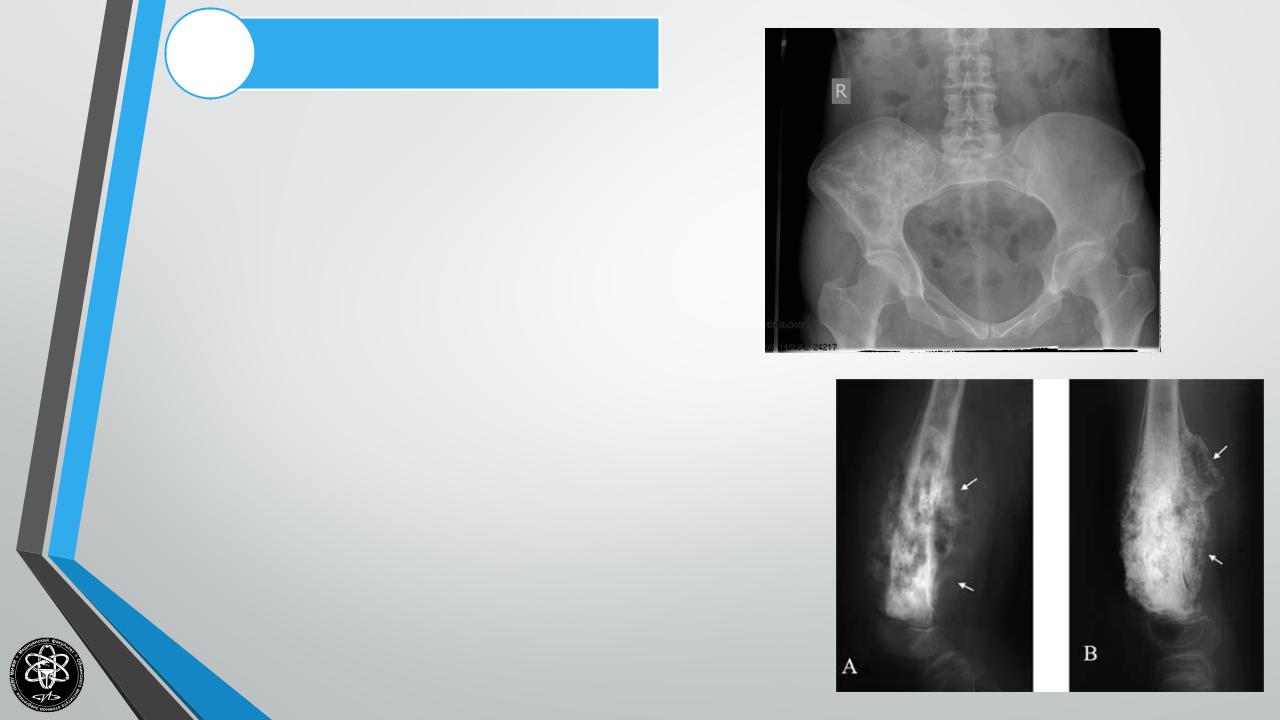

Рентгенологическоеисследование

Рентгенографический метод уточняет не только локализацию опухоли, ее размер, но, главное, дает понятие о характере опухоли, происхождении ее и изменении костной структуры. Различные доброкачественные опухоли имеют совершенно непохожую друг на друга рентгенологическую картину. Однако все они объединяются общими признаками: четкостью границ опухоли, сохранением кортикального слоя на всем протяжении опухоли, отсутствием периостальной реакции.

Злокачественные новообразования костей имеют основные сходные черты рентгенологической картины:

-нечеткость и неоднородность структуры опухоли из-за происходящей деструкции кости (так, при остеогенной саркоме в очаге поражения появляется пятнистый остеопороз с островками склероза, кость уподобляется ткани, съеденной молью).

-рано разрушается кортикальный слой с образованием типичного «козырька».

-характерным является возникновение спикул за счет растущей опухоли и отслойки надкостницы.